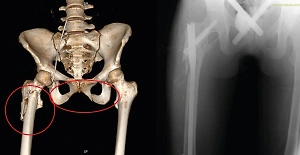

Отрубленная кисть. Фото © Telegram / Ni Mash

Как сообщил сын пострадавшего, кисть «буквально висела на коже» после несчастного случая. Травматологи в ходе трёхчасовой операции восстановили кровоснабжение и сшили повреждённые сухожилия, нервы и сосуды.